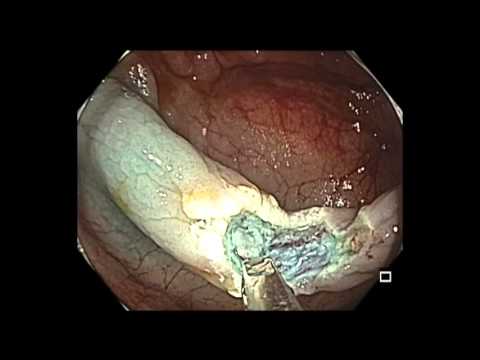

Okrężnica wstępująca - subtelny naciek - SSA

Film przedstawia resekcję płaskiego polipa typu SSA w okrężnicy wstępującej u pacjenta w średnim wieku.